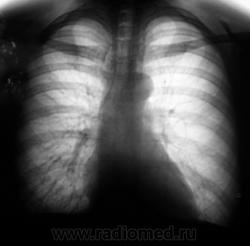

Прямо и левый бок.

Бесспорно первичная опухоль или МТС в С-3 слева.

По боковой только периферический рак( бугристы контуры)

Периферический рак в С-3 слева

Полагаю, правильный ответ здесь уже прозвучал многократно: периферический рак в/доли левого легкого с мтс в л/узлы корня

Я сравниваю, но вижу наложение на головку корня образования на ФЛГ за 2010. А расширения тела и подтверждения изменений в корне на томограммах не нахожу. Жаль, нет пары срезов корней в прямой проекции.

А Вы абстрагируйтесь от образования. Посмотрите на снимки, не увеличивая их. Обратите внимание, что талия сердца в 2010г. заполнена +тканью, т.е. лимфоузлами.